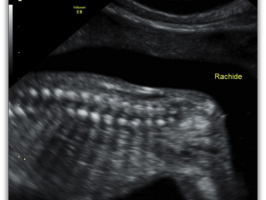

Rachide Sacrale